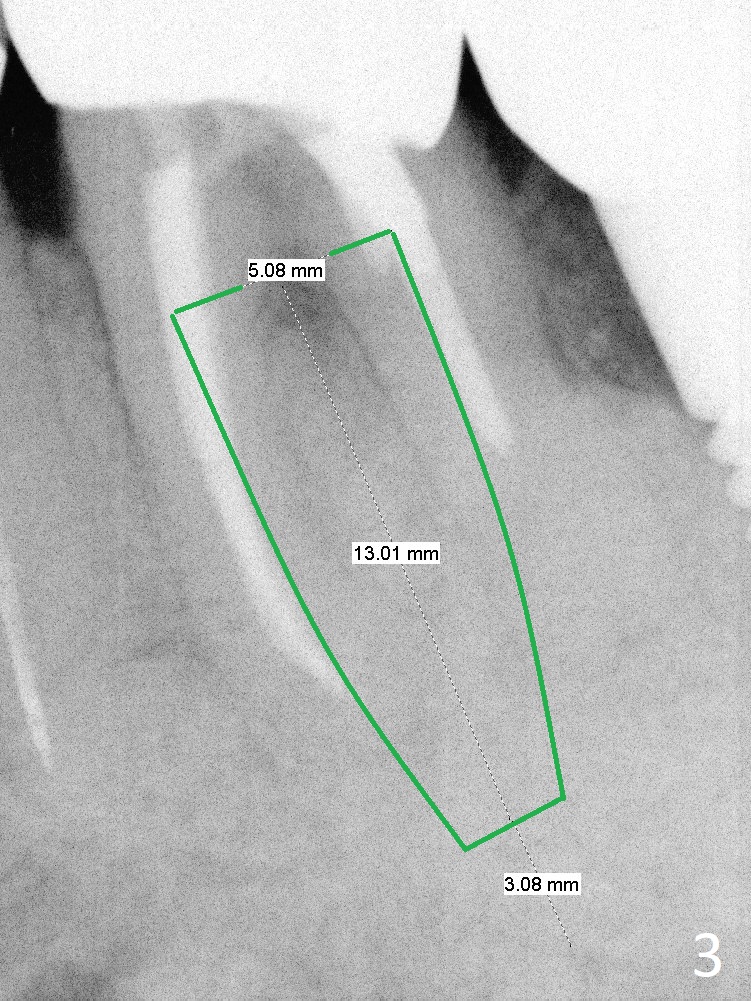

A 87-year-old man loses #19 crown and post recently (Fig.1). A new implant system will be tried. It has 2 main features. There are 2 sets of drills (short and long). Every time try short ones unless the neighboring teeth are extremely long. There are several lengths of stoppers (as short as 5.7 mm) so that we do not have to use short stoppers from DIO Sinus Master Kit. If a sample implant (5x10 mm, Fig.2) does not achieve primary stability, shift to UF, but still use IS drill for 13 mm (Fig.3). Take preop PA. Prepare surgical handpiece for sectioning. Place bone graft to the defect between #18 and 19.